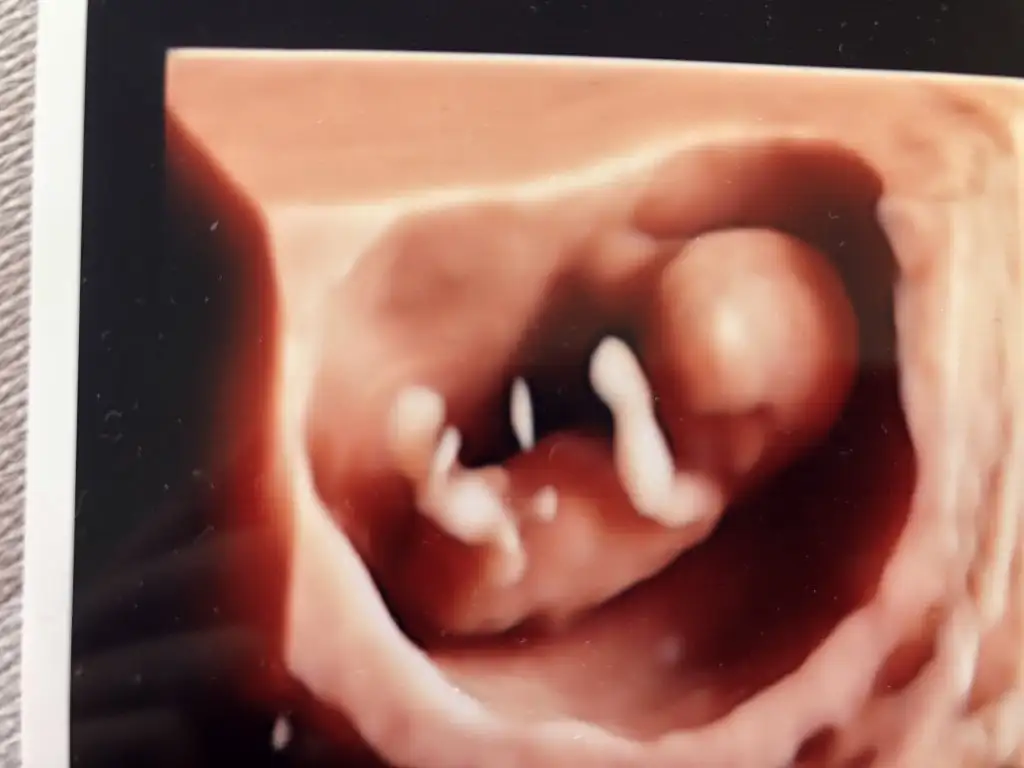

Ikra meyra Ikra meyra benim bebeğime erkek demiştin erkek çıktı 3 yaşına girecek:) arkadasımınkıne kız demiştin oda kız 2 yaşında. Yengeminkine kız dedin oda 8 aylık doğucak inş.😊 Buda kuzenimn başka fotosu yokmus malesef 😞

Ayy çok sevindim saglıkla buyusunler 😍Kaç haftalık bu usg emin değilim sanki erkek gibi 😊 anketimi oyladınmı canım